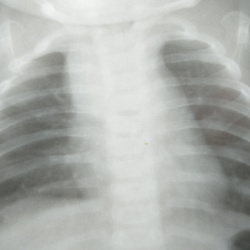

16 лет, жалоб нет, плотные участки слева -это точки оссификации хрящевой части рёбер?